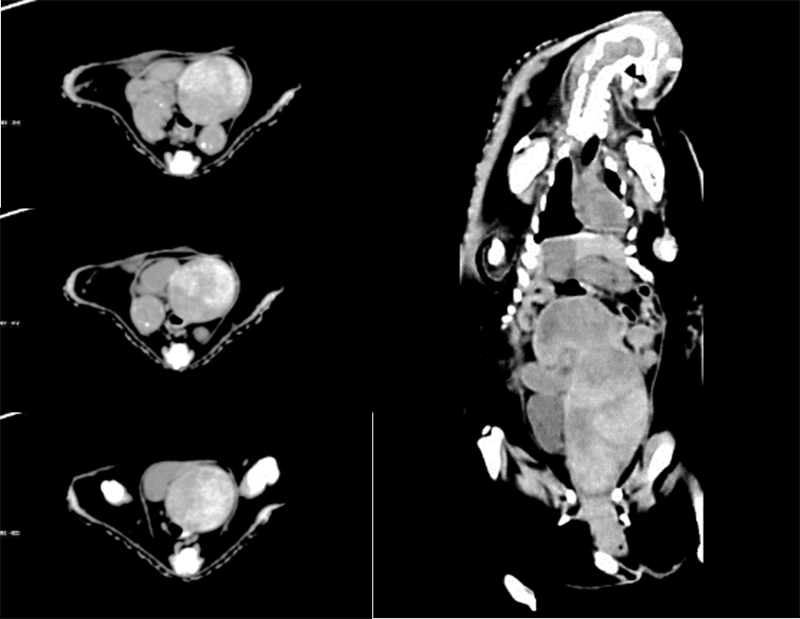

VetCare CT | 16 & 32 slices

VetCare CT series utilizes a high-performance, energy-saving X-ray tube. It minimizes the tube's power consumption, which helps to control service and operation costs. The consistent x-ray output stays uncompromised, retaining image quality.

High precision bearing facilitates long service life and system service stability. VetCare CT features a special thermal airflow design to ensure the system's high-level performance.